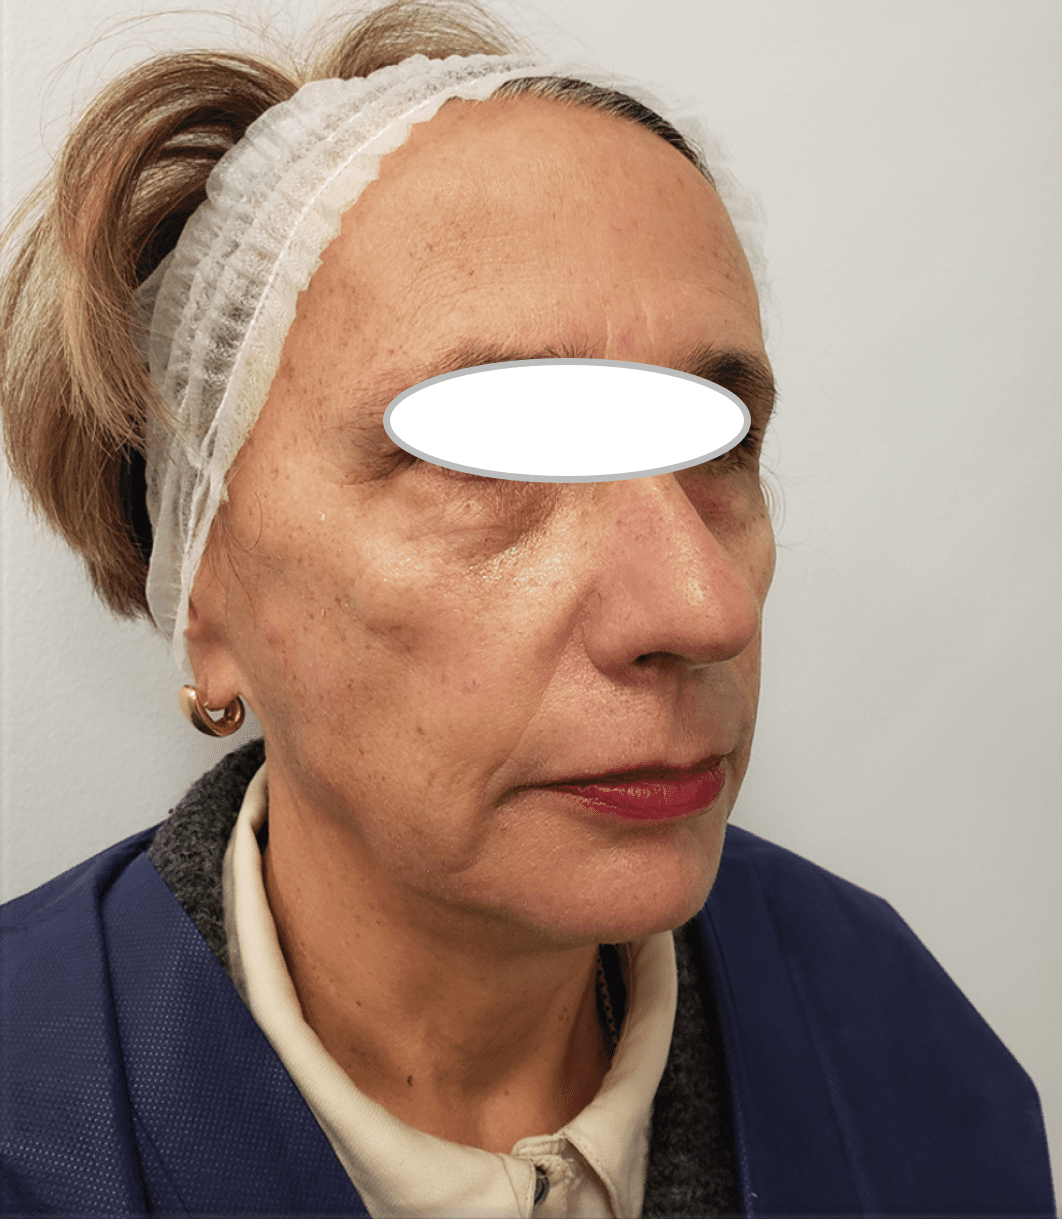

Ultherapy

Before

After